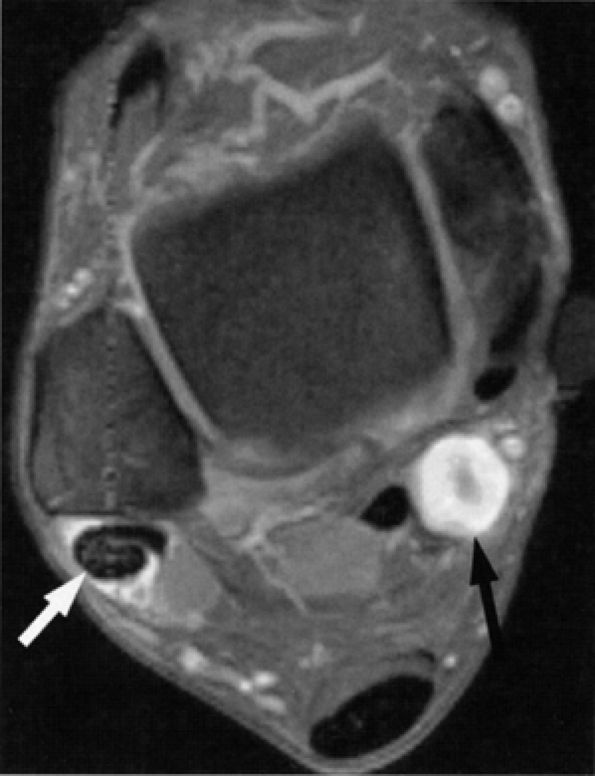

In our experience, incidental MR detection of denervation edema and atrophy of the abductor digiti quinti muscle is not uncommon and most likely reflects a clinically missed entrapment of the first branch of the lateral plantar nerve (Figs. 6.55 and 6.56).

FIGURE 6.56 ● Neuropathy of the inferior calcaneal nerve (Baxter's neuropathy) in a 66-year-old patient with tarsal tunnel varicosities. Sagittal (A) and axial (B) T1-weighted images of the ankle demonstrate denervation atrophy of the abductor digiti quinti muscle (asterisk). (C and D). Normal abductor digiti quinti muscle (asterisk) in an asymptomatic patient for comparison.